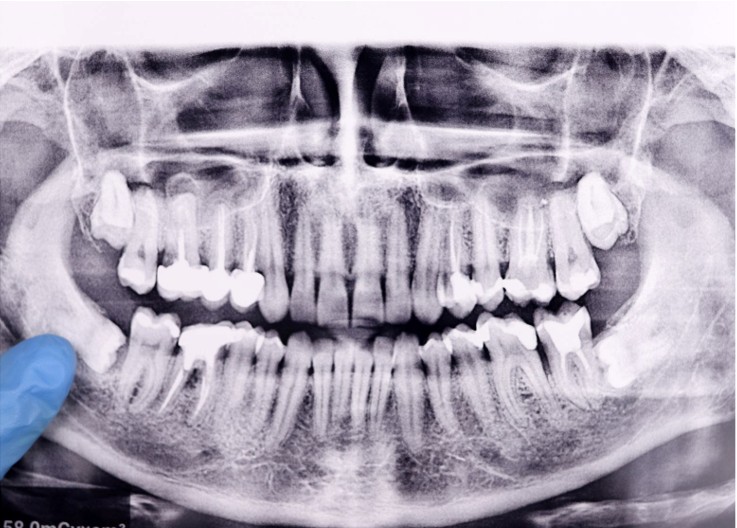

wisdom opg

Not every wisdom tooth needs extraction. At Surrey Dental Practice, a Dentist in Guildford will assess your teeth using clinical examination and dental X-rays to determine the best course of action.

In some cases, your Dentist may recommend an OPG (Panoramic Xray) or CBCT (Cone Beam CT) scan to obtain a detailed 3-dimensional image of the wisdom teeth and surrounding structures, which helps assess their exact position and their relationship to nearby nerves and sinuses, allowing for safer and more precise treatment planning.